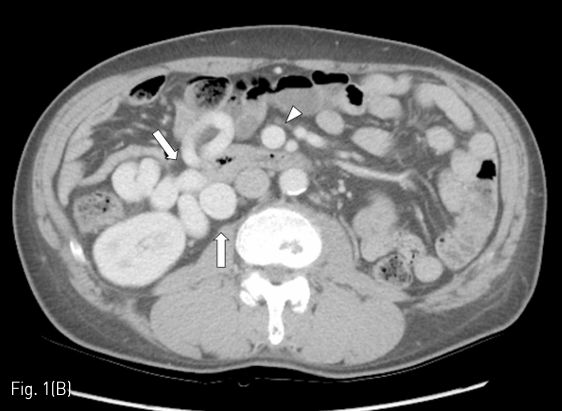

시술 전 시행한 dynamic liver CT에서 간경화 소견과 현저한 gastric varices, mesenteric-retroperitoneal varices가 관찰되었다 (Fig. 1A-C). Gastric varices는 gastro-renal shunt가, mesenteric-retroperitoneal varices는 meso-caval shunt가 각각의 경로로 생각되었다. Meso-caval shunt는 superior mesenteric vein (SMV)에서 right renal vein을 거쳐 inferior vena cava (IVC)로 유출되는 것으로 판단하였다. Esophageal varices도 보이긴 하였으나 경미한 정도였다.

Fig 1C

(A-C) Contrast-enhanced CT images obtained before PARTO show gastric varices (black arrows) and mesenteric-retroperitoneal varices (white arrows). Arrow head indicates dilated SMV. Curved arrow indicates the meso-caval shunt.